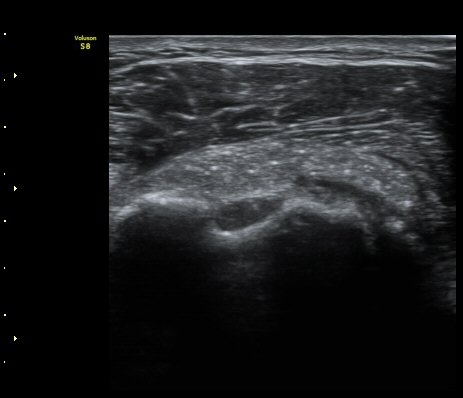

À̵ιڱ٠Á¾´Ü¸é°Ë»ç¿¡¼­µµ Á¡¾×³¶³» ¼®È­È­ À½¿µÀÌ °üÂûµÊ(±×¸² 4).

ÁÖ»ç ÈíÀΰú Á¡¾×³¶³» ÁÖ»çÄ¡·á(÷ºÎ ÆÄÀÏ) 1ÀÏ ÈÄ ½ÃÇàÇÑ °Ë»ç¿¡¼­ Á¡¾×³¶ÀÇ ºÎÁ¾ ¹× ¼®È¸ÀÇ

Á¦°Å°¡ °üÂû µÊ(±×¸² 6, 7).